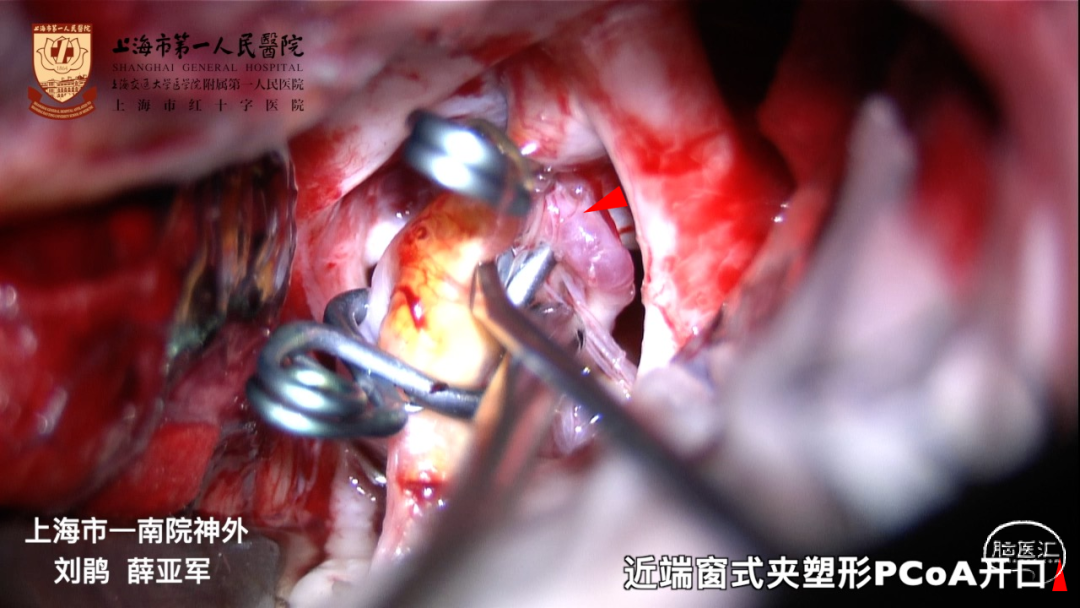

夹闭术有利于彻底夹闭瘤体,保留后交通动脉

窗式夹利弊:

窗式夹可用于后壁宽颈动脉瘤

窗式夹释放较困难,不利于保护ICA后、内侧壁发出的穿支